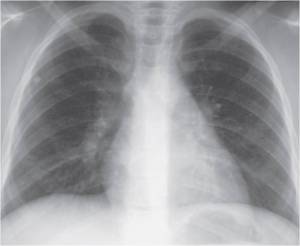

The following are examples of how Active TB may look on CXR:

Primary TB – LLL Infiltrate.

Mimics any pneumonia; occurs in debilitated pts, when Mtb first enters lung, and innate immune system unable to contain it.